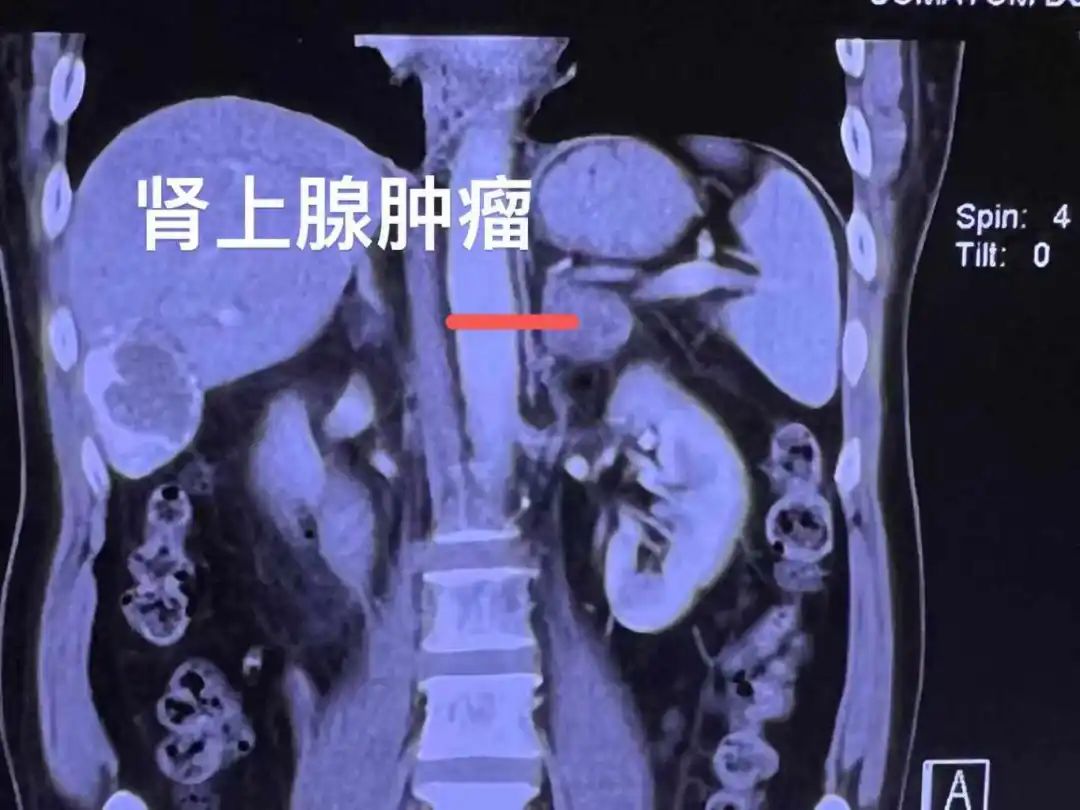

▲利用水隔离技术推开血管和胰腺,让肾上腺转移瘤的冷冻消融更加安全。

除了气体,这些年水在超声介入中扮演着很好的工具作用:通过隔离、冷却,对于一些不能消融或难以消融的肿瘤完成消融;通过建立人工腹水,对无(少)腹水的患者进行腹腔置管行腹腔热灌注治疗。

水隔离技术主要包括人工腹水、人工胸水和局部注水,或上述三种技术联合。超声引导下水隔离技术主要是利用了水的高比热容特性,在实时超声引导下利用经皮穿刺针(PTC)把生理盐水注射到预定部位,能非常安全地在需要消融的部位与重要结构或器官之间形成一道液体“保护屏障”,达到肿瘤完全消融灭活且不损伤邻近器官及组织的效果。